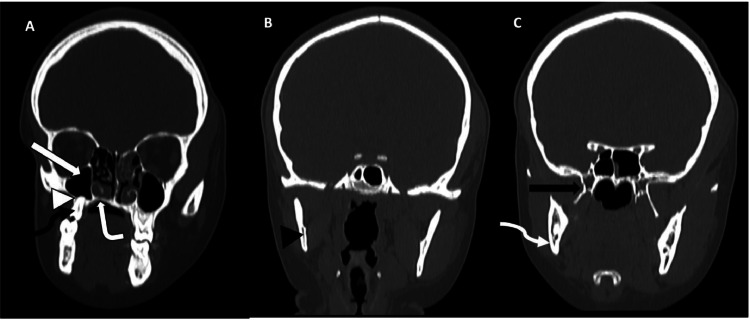

Fig. 3.

(A-C) Coronal reformatted CT scans of the head (bone window) shows reduction in the sizes of the palatine process (white bent arrow) and the alveolar process (white arrowhead) of the right maxilla with a smaller right maxillary sinus (white block arrow) and first right upper molar (black squiggle arrow) (A). There is also reduction in the size of the right mandibular ramus (black arrowhead) (B), the right mandibular angle (white squiggle arrow), the body, medial and lateral processes of the right pterygoid bone (black block arrow) (C).